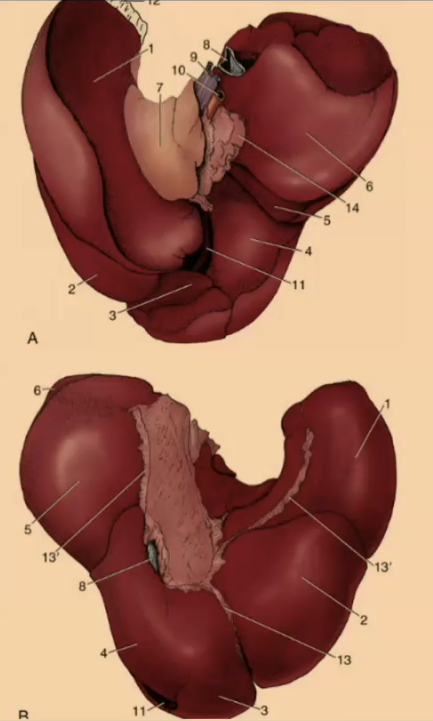

How many lobes are there to the liver?

4

What are the 4 lobes of the liver?

Left, Quadrate, Right, Caudate

#2?

Medial

#1?

Lateral

#3?

Quadrate

#4?

Medial

#5

Lateral

#6 & #7

Caudate